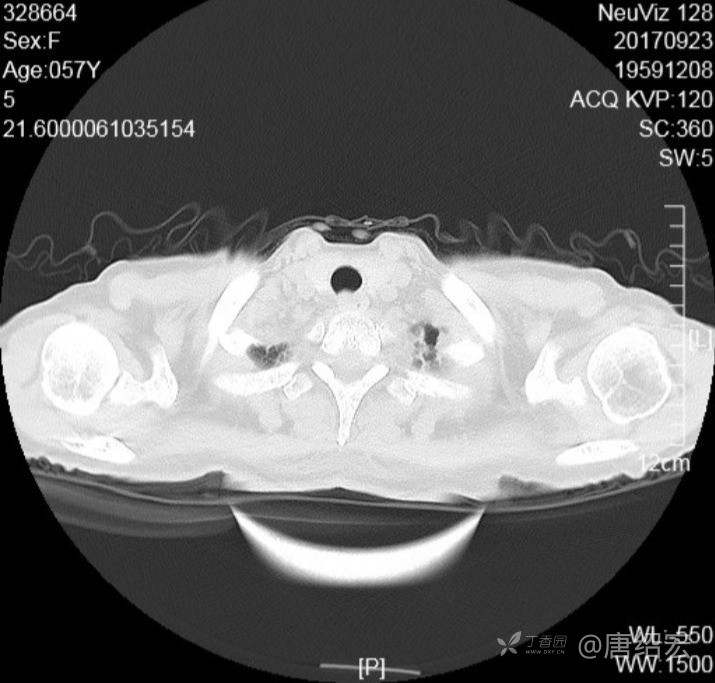

中年女性满肺树芽征还有支气管扩张,考虑什么疾病?

女,57岁,

主诉:发热、咳嗽、咯黄痰,胸闷3天入院。